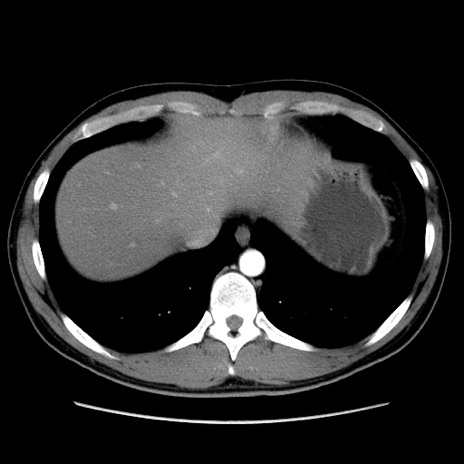

冠状断像

【症例】20歳代 男性

【主訴】心窩部痛

【現病歴】今朝より上腹部痛あり。一旦軽快していたが再度出現したため救急要請。昨日夕に白身の魚を含む刺身を食べた。

【身体所見】BP 136/89mmHg、HR 74/min、BT 37.0℃、腹部:膨満、軟、心窩部に圧痛あり。反跳痛なし、筋性防御なし、腸雑音やや亢進あり。

【データ】WBC 17700、CRP 0.48